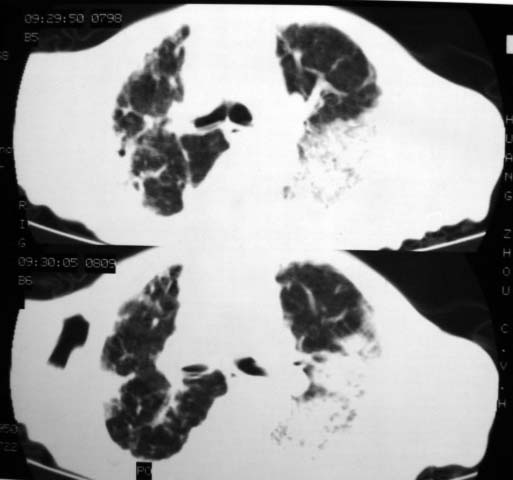

男,85岁,发热2月, 血常规:hgb99g/l.rbc2.55×1012/l.wbc3.8×109/l.n78.2%  l20.7% m1.1%.  hct26.3% .血沉20mm/hg.痰检结核杆菌阴性。ddp阳性。痰少粘稠色白。无咳血。

1.右上肺陈旧性肺结核灶;

2.左上肺、双下肺及右中叶肺炎(左上肺肺炎治疗后好转)

右上肺陈旧性肺结核灶,双肺感染灶〔大部份纤维化〕,肺气肿.

双肺继发型结核

双肺继发型肺结核,肺纤维化,肺气肿,胸膜肥厚黏连。